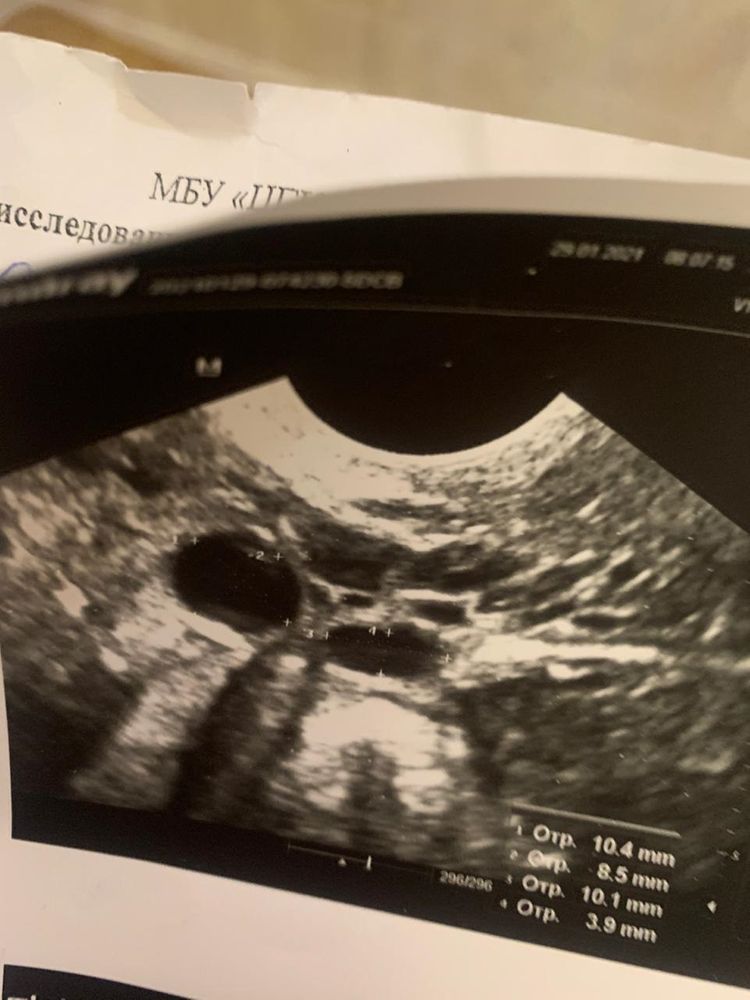

в заключение про трубу ничего не написано.Но есть каких то 2 ж/о в полости матке ,что это не кто не обьяснил.Как вы думаете что это?

Вот фотография узи и заключение

ж/о - жидкостные образования

Про образования в матке ни слова нет. 2 жидкостных образования рядом с правым яичником- это скорее всего кисты.